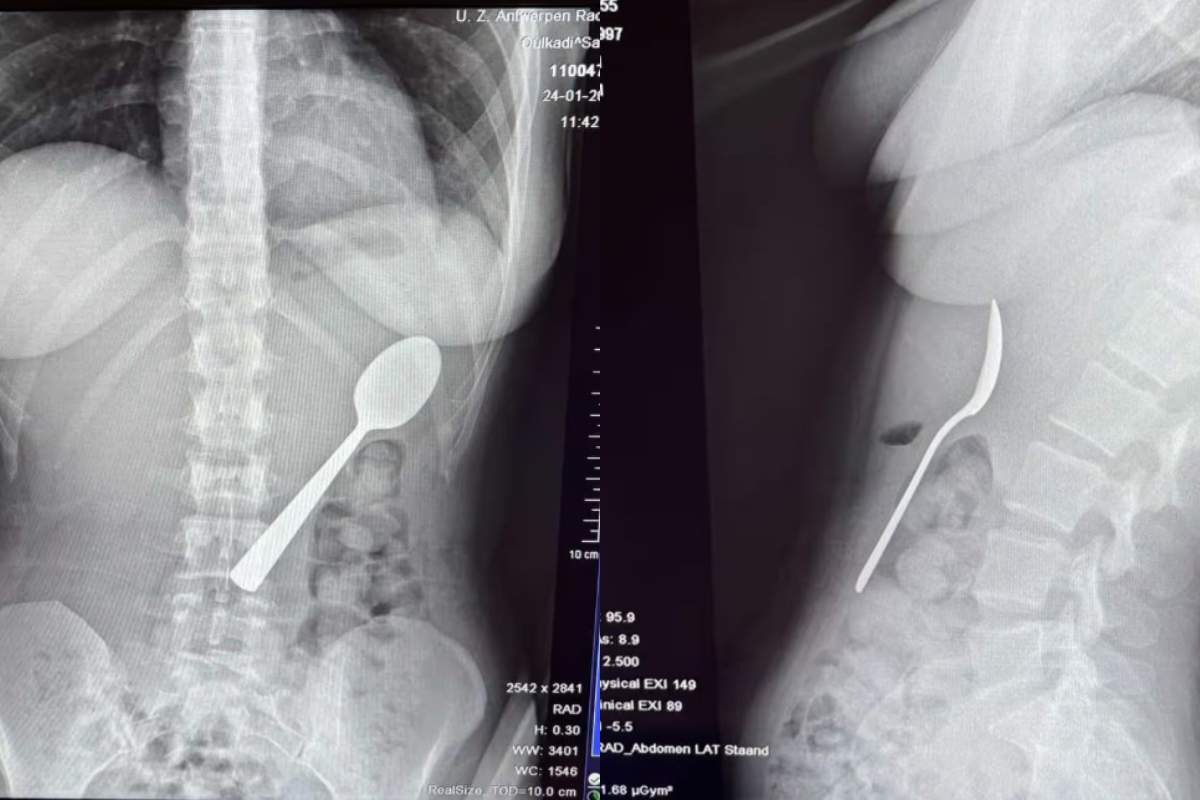

O femeie a înghițit accidental o lingură lungă de 17 cm când câinele ei a sărit în poala ei în timp ce mânca iaurt. Reymy Amelinckx a spus că a trebuit să aleagă între „a se sufoca sau a înghiți lingura”, deoarece a simțit cum tacâmul „aluneca ușor în stomac”.

O femeie a înghițit din greșeală o lingură lungă de 17 cm

Tânăra în vârstă de 28 de ani a povestit că stătea pe canapea și mânca iaurt în momentul în care câinele ei, un vizsla maghiar, pe nume Marley, a sărit brusc pe ea.

Femeia povestește că a încercat inițial să scoată lingura de 17 cm cu mâna.